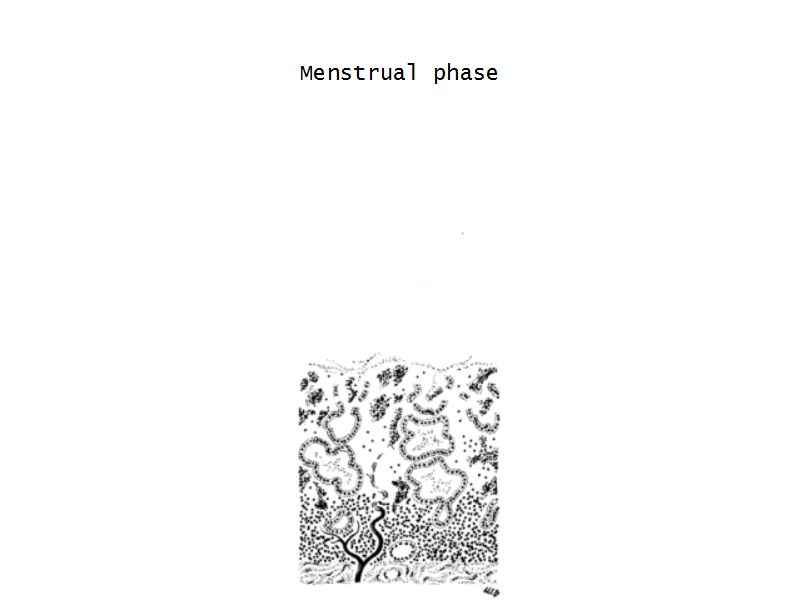

Menstrual cycle

- Menstrual phase

Menstrual phase

- Vasoconstriction

- Ischaemia

- Necrosis functional layer

- Basal layer

- No necrosis

- Short straight vessels